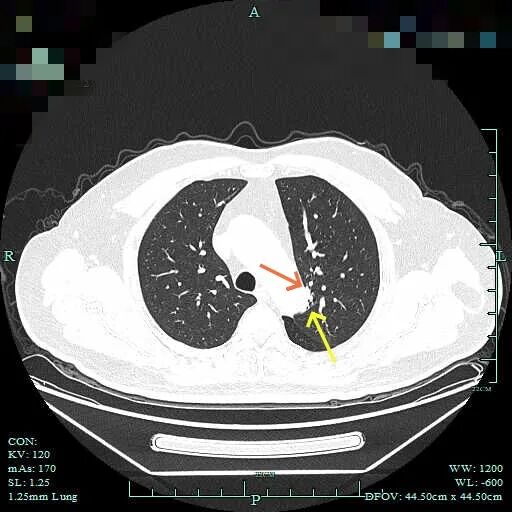

先看2022年12月时的影像:

这个片子质量较差,雪花点很多,清晰度不够。但这个病灶整体轮廓较清,密度不纯,贴近主动脉与叶间裂,灶内有细小空泡征,是要高度怀疑恶性,短期抗炎治疗后复查若无吸收好转,宜及时手术为稳妥。